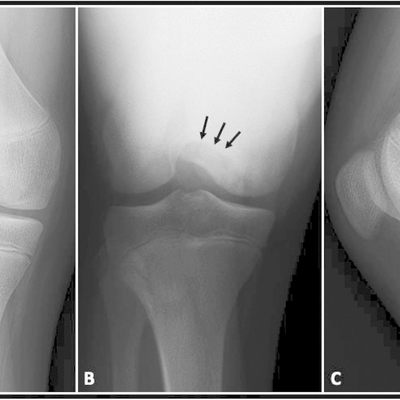

Click on an image below to view more info.